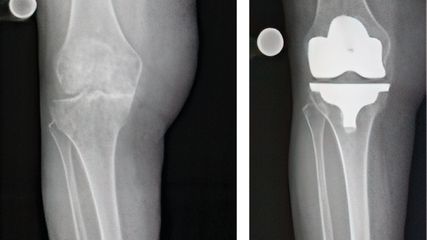

Abb. 1:Anterior-posteriores Röntgenbild des rechten Kniegelenks eines 12-jährigen Mädchens mit symptomatischem Scheibenmeniskus. Es zeigt sich lateral eine Erweiterung des Gelenksspaltes sowie eine milde Abflachung des lateralen Femurkondylus („Squaring“)

In der Regel werden zunächst eine a/p und eine seitliche Röntgenaufnahme angefertigt. Damit können einerseits Differenzialdiagnosen wie eine Fraktur, Osteochondritis dissecans oder ein Tumor ausgeschlossen werden. Es gibt aber auch charakteristische Röntgenzeichen, die auf das Vorliegen eines Scheibenmeniskus hinweisen können. Dazu zählen ein erweiterter lateraler Gelenkspalt, ein hypoplastisches Tuberculum intercondylare laterale, eine vermehrte Konkavität des lateralen Tibiaplateaus sowie ein „Squaring“ des lateralen Femurkondylus (Abb. 1).19